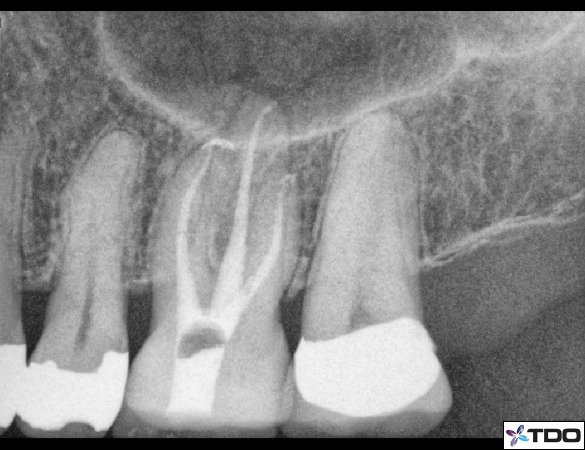

Returning back to what we feel is the singular reason for conservation of tooth with the access is that it results in a stronger tooth. Let’s consider a few of the places where a tooth derives a lot of strength. The marginal ridges of molars, premolars and anterior teeth serve as a bulk of support for those teeth. Interference of those areas will of course weaken a tooth. A class 3 MOD filling on a molar will certainly weaken a tooth more than a class 1 occlusal filling. Thus if we can try to keep our endodontic access cavities more centralized and keep marginal ridges with a bulk of tooth structure then we can keep the tooth stronger. This is slightly different than what is taught in schools in which the mesial marginal ridge is not kept as sacred. Another important area to try to avoid is accessing too close to the cuspal tips of molars, incisal edges of anteriors, or too far linqually/palatally on the incisor cingulum. Again a more centralized access form will result in a stronger tooth remaining. Additionally, when working upon porcelain crowns there is less fracture potential with more bulk of porcelain. Thus less infringement upon the lateral surfaces of the porcelain will allow more bulk of material. (See figures 7, 8)

Figure 7: A conservative access form with a convergence towards the occlusal and preservation of mesial tooth structure.

Figure 8: Another access form with convergence towards the occlusal. This access cavity is quite centralized in the molar in both the mesial to distal direction and buccal to lingual direction.